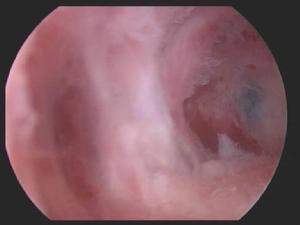

宮腔鏡下的宮腔積膿急性或慢性子宮內膜炎所導致的宮頸阻塞,如宮腔內的炎性分泌物不能外流或引流不暢,即可形成宮腔積膿。

1、子宮腔鏡檢查可了解有無宮腔積膿,並確定粘連部位、範圍、程度及粘連的組織。各組粘連的特點為:子宮內宮腔積膿與周圍的內膜很相似;肌纖維粘連最常見,其特點為有一薄層子宮內膜覆在上面,表面有很多腺體開口;而結締組織粘連則表面無內膜形成。

7、子宮鏡近年來有用子宮鏡檢查作為診斷和治療宮腔積膿的方法。